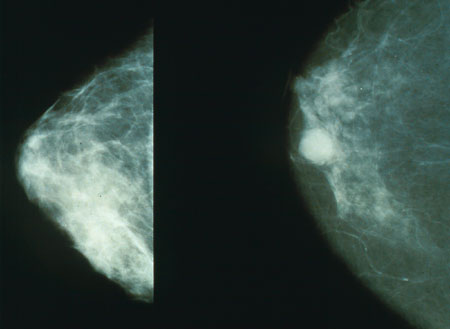

يوافق يوم 4 فبراير من كل عام اليوم العالمي للسرطان حيث تنضم منظمة الصحة العالمية إلى الاتحاد الدولي لمكافحة السرطان، وهو الجهة الراعية للاحتفالات بهذا اليوم، من أجل الترويج لسُبل التخفيف من العبء العالمي الناجم عن هذا المرض ؛ فالسرطان من أسباب الوفاة الرئيسية في جميع أنحاء العالم. وتشير تقديرات منظمة الصحة العالمية إلى أنّ هذا المرض يودي بحياة 8 مليون نسمة تقريبا سنويا . وأنقل للإخوة الزملاء تلك المقالة المفيدة عن هذاالموضوع الهام مرض السرطان ![]() (تبديد المفاهيم الخاطئة) السرطان مصطلح عام يشمل مجموعة من الأمراض يمكنها أن تصيب كل أجزاء الجسم، ويشار إلى تلك الأمراض أيضًا بالأورام. ومن السمات التي تميز السرطان التكاثر السريع لخلايا شاذة يمكنها النمو خارج حدودها المعروفة واقتحام أجزاء الجسد المتلاصقة والانتشار إلى أعضاء أخرى، ويطلق على تلك الظاهرة اسم (النقيلة). جدير بالذكر أن النقائل تمثل أهم أسباب الوفاة للسرطان. أسباب الإصابة بالسرطان: ينشأ السرطان من خلية واحدة. ويتم تحول الخلية الطبيعية إلى خلية سرطانية في مراحل متعددة، وعادة ما يتم ذلك التحول من آفة محتملة التسرطن إلى أورام خبيثة. وهذه التغيرات ناجمة عن التفاعل بين عوامل الفرد الجينية وبعض العوامل الخارجية. وتزيد نسبة الإصابة بالسرطان بشكل كبير مع التقدم في السن، ويعود ذلك - على الأرجح - إلى زيادة مخاطر الإصابة بسرطانات معينة مع التقدم بالعمر، وتراكم مخاطر الإصابة بالسرطان يتم إلى جانب انخفاض فعالية آليات الإصلاح الخلوي كلما تقدم الشخص في السن. جدير بالذكر أن تعاطي التبغ والكحول وقلة تناول الخضراوات والفاكهة والإصابة بفيروسي التهاب الكبد C وB والفيروس المسبب لسرطان عنق الرحم من عوامل الاختطار الرئيسة التي تقف وراء الإصابة بالسرطان في البلدان المنخفضة والمتوسطة الدخل. كما أن سرطان عنق الرحم الناجم عن فيروس الورم الحليمي البشري من أهم أسباب وفاة النساء جراء السرطان في البلدان المخفضة الدخل. ويمكن تلخيص أسباب الإصابة بالسرطان في التالي: تعاطي التبغ. فرط الوزن والسمنة. قلة تناول الخضراوات والفاكهة. الخمول البدني. تعاطي الكحول. أنواع العدوى المنقولة جنسيًا مثل العدوى بفيروس الإيدز والفيروس المسبب لسرطان عنق الرحم. تلوث الهواء في المدن المتقدمة. التعرض للدخان الناجم عن حرق الوقود الصلب داخل المباني. عوامل الخطورة: العمر: معظم حالات السرطان تكتشف عند سن 55 وأكبر، إلا أن السرطان ممكن أن يكتشف عند أية مرحلة عمرية. نمط الحياة: يزيد معدل السرطان لدى الأشخاص ذوي السلوكيات غير الصحية كالتدخين وشرب الكحول والتعرض المباشر لأشعة الشمس والعلاقات المحرمة. التاريخ العائلي: تتحمل الوراثة 5-10% من نسبة الإصابة بالسرطان ولكن ليس بالضرورة أن كل من لديه عامل وراثي يصاب بالسرطان. الحالة الصحية: هناك علاقة بين الأمراض المزمنة والسرطان مثل مرض التهاب القولون المزمن. الأعراض والعلامات: تختلف الأعراض حسب العضو المصاب في الجسم ما بين حمى، وألم، وشعور بالتعب والإرهاق، وتغير مفاجئ في الوزن (نقص في الغالب). كما تظهر كتلة أو سمك محسوس تحت الجلد، ويتغير لون الجلد (اصفرار، احمرار، التحول إلى اللون الداكن) أو وجود جروح لا تلتئم، كحة مستمرة، بحة في الصوت، صعوبة في البلع، عسر في الهضم، تغير في عادة التبرز والإخراج. التشخيص: قد يجري الطبيب أحد الإجراءات التالية لتشخيص المرض حسب حالة المريض وهي: الفحص السريري: يفحص الطبيب جسم المريض ويبحث عن أي كتلة أو تغير في لون الجلد أو زيادة في الحجم تدل على حدوث السرطان. فحوصات المختبر: ويتم ذلك بأخذ عينة من الدم للكشف عن السرطان مثل سرطان الدم. الأشعة: تعمل الأشعة على فحص العظام والأعضاء الداخلية مثل الأشعة الصوتية، وأشعة العظام، والتصوير بالرنين المغناطيسي، والأشعة المقطعية. الخزعة: هناك طرق مختلفة لجمع عينة الخزعة، ويعتمد أخذ الخزعة على نوع السرطان وموقعه في الجسم. وفي معظم حالات السرطان يكون أفضل طريقة لتشخيص المرض وأضمنها. يساعد تشخيص السرطان في مرحلة مبكرة على سرعة علاج الحالة ومن ثم الشفاء - بإذن الله. يساعد الفحص الطبي الدوري على اكتشاف السرطان في مرحلة مبكرة. ويجرى بصورة منتظمة للفئات الأكثر عرضة للإصابة بالمرض. أوصت الجمعية الأمريكية للسرطان بمجموعة فحوصات طبية تجرى للوقاية من السرطان للبالغين. الفئات الأكثر عرضــــــــــــــــــــــة نوع السرطــــــــــــان النساء عند عمر 40 سنة أو أكبر سرطان الثدي النساء عند عمر 21 أو أكبر سرطان عنق الرحم النساء والرجال عند عمر 50 سنة أو أكبر سرطان القولون الرجال عند عمر 50 سنة أو أكبر سرطان البروستاتا مراحل الإصابة بالسرطان: يبحث الطبيب عن مراحل انتشار المرض في الجسم، وبصفة عامة يصنف السرطان بأربع مراحل تبدأ من (المرحلة الأولى) إلى (المرحلة الرابعة) وتعد المرحلة الرابعة الأشد خطورة. مضاعفات السرطان: التفاعل غير الطبيعي للجهاز المناعي مع السرطان: في بعض الحالات يتفاعل الجهاز المناعي ويهاجم الخلايا السليمة. انتشار المرض: قد يهاجم السرطان أجزاء أخرى من الجسم. وغالبًا يمكن التحكم به لكن لا يمكن علاجه. عودة المرض مرة أخرى: بعض أنواع السرطان من الممكن أن يعاود الظهور مرة أخرى، لذلك من المهم متابعة الحالة بعد العلاج وعمل الفحوصات الطبية الدورية. العلاج: يعتمد علاج السرطان على عدة عوامل لعل أبرزها نوع السرطان ومرحلته وحالة المريض الصحية. الغرض من علاج السرطان: العلاج الأولي: ويتم عادة عن طريق الجراحة بغرض التخلص من الخلايا السرطانية. العلاج المساند: يعمل على قتل الخلايا السرطانية المتبقية بعد العلاج الأولي كالعلاج الكيميائي أو الإشعاعي أو الهرموني. العلاج التلطيفي: وهو العلاج بغرض التحكم في مضاعفات المرض. خيارات علاج السرطان: العلاج الجراحي: للتخلص من الورم. العلاج الكيمائي: وهي أدوية تعمل على قتل الخلايا السرطانية. العلاج الإشعاعي: باستخدام أشعة عالية الطاقة مثل أشعة إكس. زراعة خلايا الجذع: وذلك بوساطة نقل نخاع العظم ويمكن أن يؤخذ من المريض أو من متبرع. العلاج البيولوجي: يساعد الجهاز المناعي للجسم على الكشف عن الخلايا السرطانية ومحاربتها. العلاج الهرموني: بعض أنواع السرطان تتغذى على هرمونات الجسم مثل سرطان الثدي والبروستاتا، فعند التخلص من هرمون الجسم تموت الخلية السرطانية. الوقاية: لا توجد طريقة محددة للوقاية من السرطان لكن هناك عوامل تقلل من خطورة المرض وهي كالتالي: امتنع عن التدخين: فهناك علاقة قوية بين السرطان والتدخين، خصوصًا سرطان الرئة. تجنب التعرض المباشر للأشعة، خصوصًا الأشعة فوق البنفسجية الضارة وذلك بالجلوس في الظل، وارتداء الملابس الواقية واستخدام كريم واقٍ من أشعة الشمس. التغذية السليمة: باختيار الأغذية الغنية بالفاكهة والخضراوات واختيار الحبوب الكاملة كالشوفان والأرز البني والقمح المجروش. مارس الرياضة بانتظام: ممارسة الرياضة لمدة 30 دقيقة يوميًا تساعد على تقليل فرصة حدوث السرطان. حافظ على الوزن المثالي: أثبتت الأبحاث أن هناك علاقة وطيدة بين السمنة (زيادة الوزن) والسرطان، ويمكن الوصول إلى الوزن المثالي بالرياضة المنتظمة والتغذية السليمة. إجراء الفحص الطبي بانتظام. التطعيمات: توجد فيروسات محددة تسبب السرطان مثل فيروس التهاب الكبدي الوبائي (ب) الذي يسبب سرطان الكبد والفيروس المسبب لسرطان عنق الرحم، وبإمكان التطعيم أن يقيك - بإذن الله - من هذه الفيروسات. خذ قسطًا كافيًا من النوم والراحة. تجنب ضغوط الحياة ومارس هواياتك. المصدر http://www.moh.gov.sa/HealthAwarenes...01-18-001.aspx التعديل الأخير تم بواسطة أحمد صلاح الحفني ; 2014-02-04 الساعة 01:44 PM. |